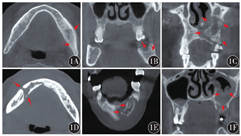

MRONJ发生于上颌骨2例,下颌骨4例,无上、下颌骨同时发病的患者。6例病损首发出现在前磨牙或磨牙区,但随着疾病进展,可扩展至前牙区及磨牙后区。影像学多表现为溶骨、硬化或二者混合性表现,伴或不伴骨膜反应;还有拔牙窝空虚或根尖透光区形成、死骨分离影像等(图1)。